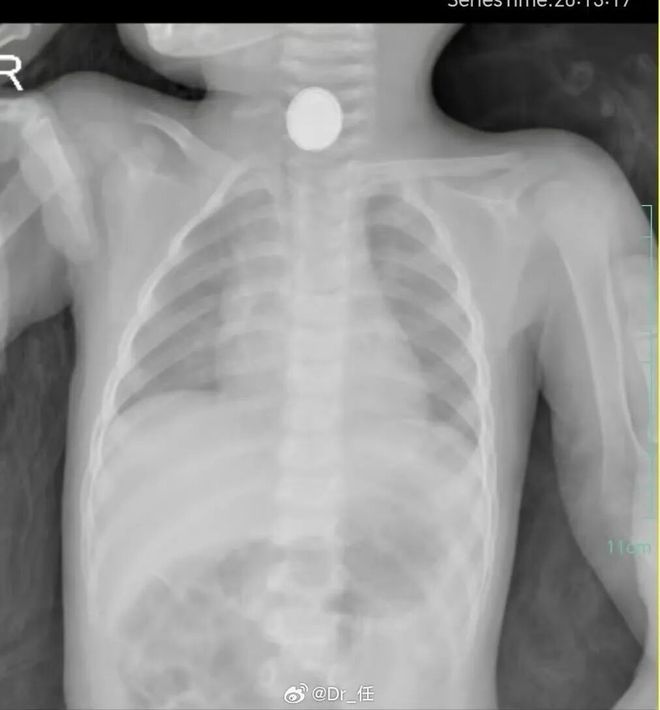

纽扣电池害娃!15 分钟灼食管中益医学研究院支招

遥控器里的纽扣电池、电子秤上的小电池、孩子玩具里的 “能量片”,这些家家都有的 “小圆片”,竟藏着能让娃丧命的风险!青岛 1 岁宝宝误吞纽扣电池 50 多小时,食管被腐蚀得发黑坏死,后续要长期治疗才能正常吃饭 —— 更吓人的是,这东西进了娃的肚子,15 分钟就能烧穿食管黏膜,30 分钟就渗进肌肉层,根本等不起!

纽扣电池大多是碱性的,进了娃湿润的嘴巴和食道,正负极一接触唾液、胃酸,就像接了电,会释放强碱性物质。中益医学研究院实验室测过,这东西 15 分钟就能把食管黏膜烧破,30 分钟就往肌肉层里钻 —— 哪怕是没电的旧电池,残留的碱性物质也能在 2 小时内造成深度灼伤,很多家长以为 “没电就安全”,其实是大错特错!

1 岁娃的食道才 10 毫米粗,纽扣电池却有 16-20 毫米大,刚好卡在食道最窄的地方。这东西一直压着黏膜,6 小时就会让黏膜缺血,24 小时可能把食道压穿孔,一旦穿孔就会引发纵隔感染、大出血,救回来也可能留后遗症。专家说,嵌顿超过 24 小时的娃,并发症风险能到 78%,比 24 小时内取出的高 6 倍多!